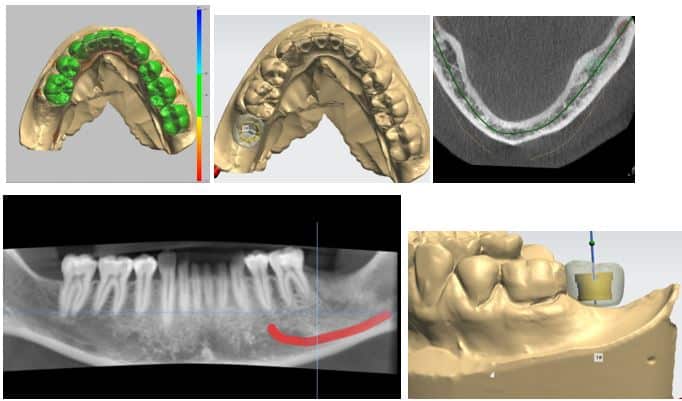

Use of Guided Implant surgery and use of a Cone Beam CT in a General Dental Practice

Each and every patient who has an implant placed in the practice undergoes a Cone Beam CT scan. The data is analyzed and each case meticulously planned. Each implant is planned and placed using the 3D data.

The guided implant placement approach has worked very well in eliminating any guess work associated with implant placement. The surgical site being so precisely planned completely minimizes the post-operative discomfort experienced by my patients. This has led to many patients having to take a low dose of an analgesic if any at all after single implant placement. This makes for a very comfortable and pleasant experience for the patient.